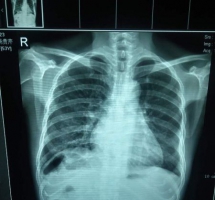

查体:BP.120/70 无眼睑浮肿,心肺未见异常,双肾区轻度叩击痛,来诊尿检蛋白(+)其余的正常,

• 请各位老师给看看这张片子。